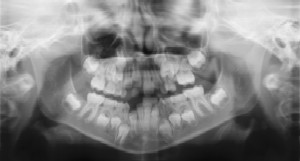

Dental Radiographs (X-Rays)

Radiographs (X-Rays) are a vital and necessary part of your child’s dental diagnostic process. Without them, certain dental conditions can and will be missed.

Radiographs detect much more than cavities. For example, radiographs may be needed to survey erupting teeth, diagnose bone diseases, evaluate the results of an injury, or plan orthodontic treatment. Radiographs allow dentists to diagnose and treat health conditions that cannot be detected during a clinical examination. If dental problems are found and treated early, dental care is more comfortable for your child and more affordable for you.

The American Academy of Pediatric Dentistry recommends radiographs and examinations every six months for children with a high risk of tooth decay. On average, most pediatric dentists request radiographs approximately once a year. Approximately every three years, it is a good idea to obtain a complete set of radiographs, either a panoramic and bitewings, or periapicals and bitewings.

Pediatric dentists are particularly careful to minimize the exposure of their patients to radiation. With contemporary safeguards, the amount of radiation received in a dental X-ray examination is extremely small. The risk is negligible. In fact, the dental radiographs represent a far smaller risk than an undetected and untreated dental problem. Lead body aprons and shields will protect your child. Today’s equipment filters out unnecessary X-rays and restricts the X-ray beam to the area of interest. High-speed film and proper shielding assure that your child receives a minimal amount of radiation exposure.